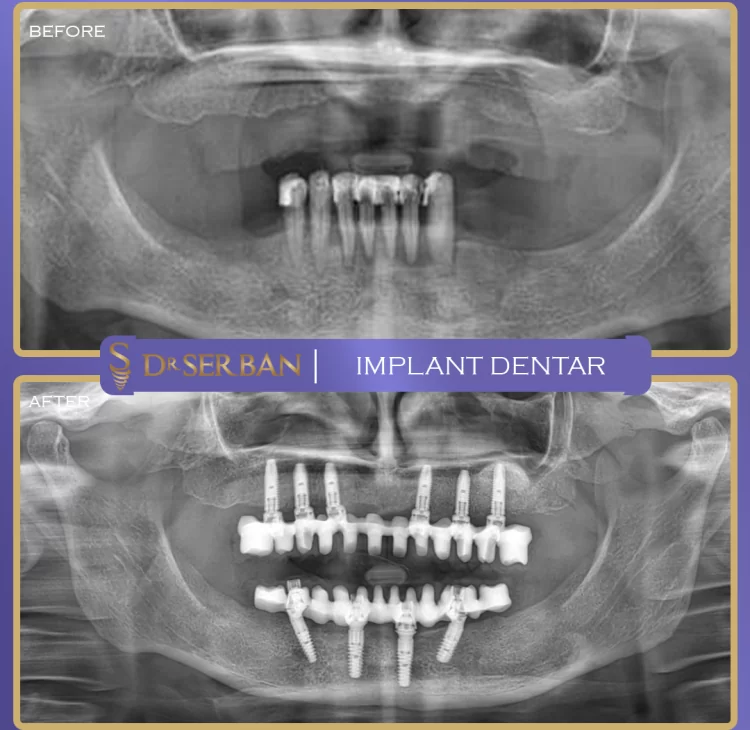

Implant dentar

Implantul dentar este o opțiune de tratament de luat în considerare atunci când lipsesc unul sau mai mulți dinți. Recomandarea se face de către medicul dentist, în urma unei evaluări, ținând cont de starea de sănătate orală și de specificațiile fiecărui caz. În anumite situații, implantul dentar poate contribui la refacerea funcției masticatorii și a aspectului dinților.

Tratamentul cu implant dentar este considerat unul dintre cele mai moderne metode de înlocuire a dinților pierduți, o variantă sigură și durabilă pentru pacienții din întreaga lume, pentru că își păstrează integritatea pe termen lung și preia toate funcțiile și caracteristicile unui dinte natural.

Implantul dentar este practic o rădăcină artificială. Poate susține o coroană sau o punte dentară. Acesta este considerat o opțiune viabilă pentru înlocuirea dinților lipsă datorită durabilității și aspectului natural pe care îl oferă.